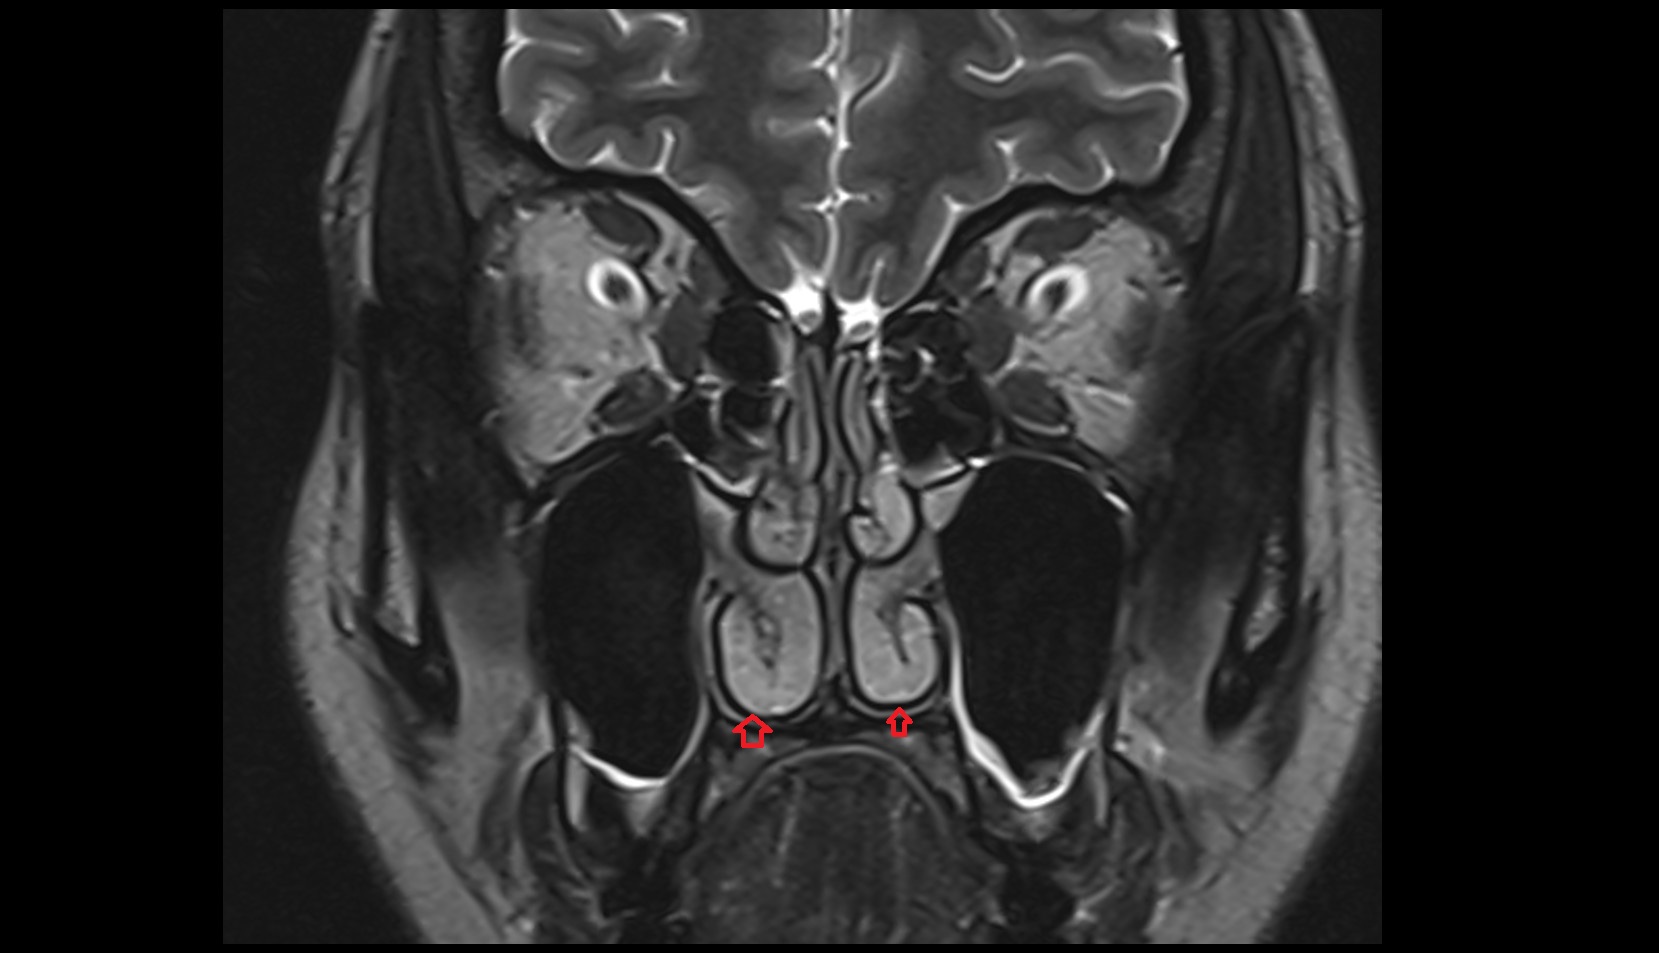

- Cerebellar tonsil (H IX)